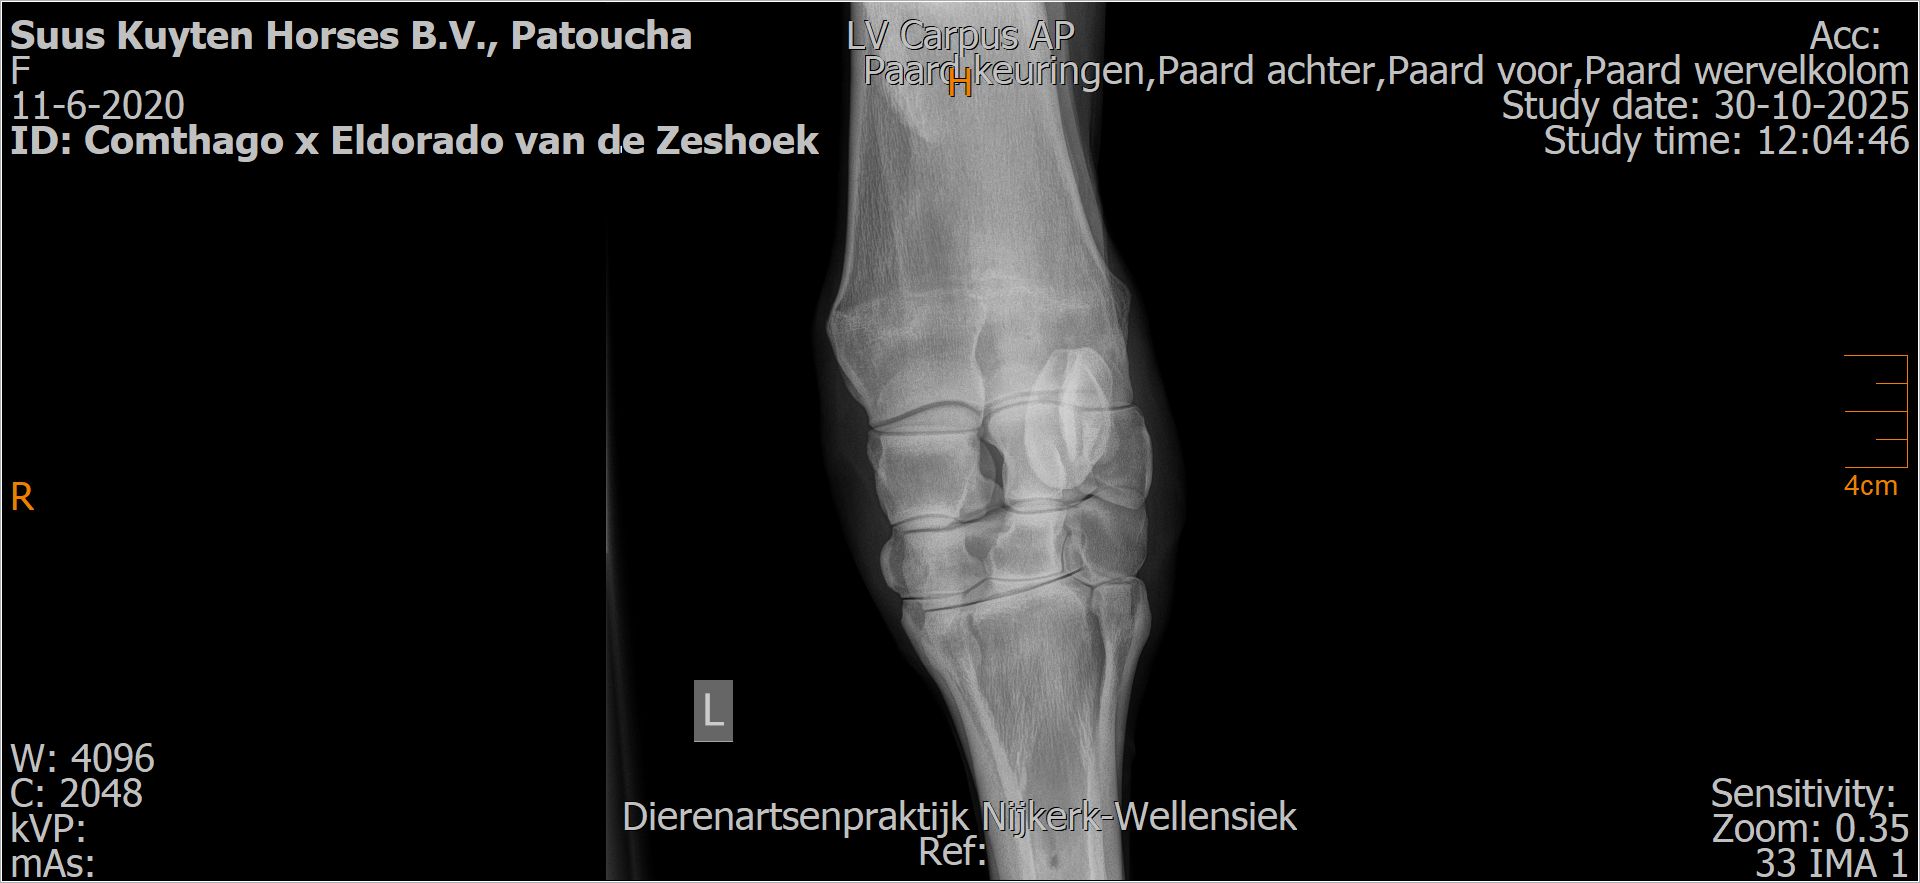

Patoucha

Leeftijd:

7

Röntgenfoto’s